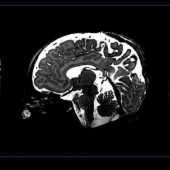

Major advance for detecting brain conditions in babies

Neuroimaging